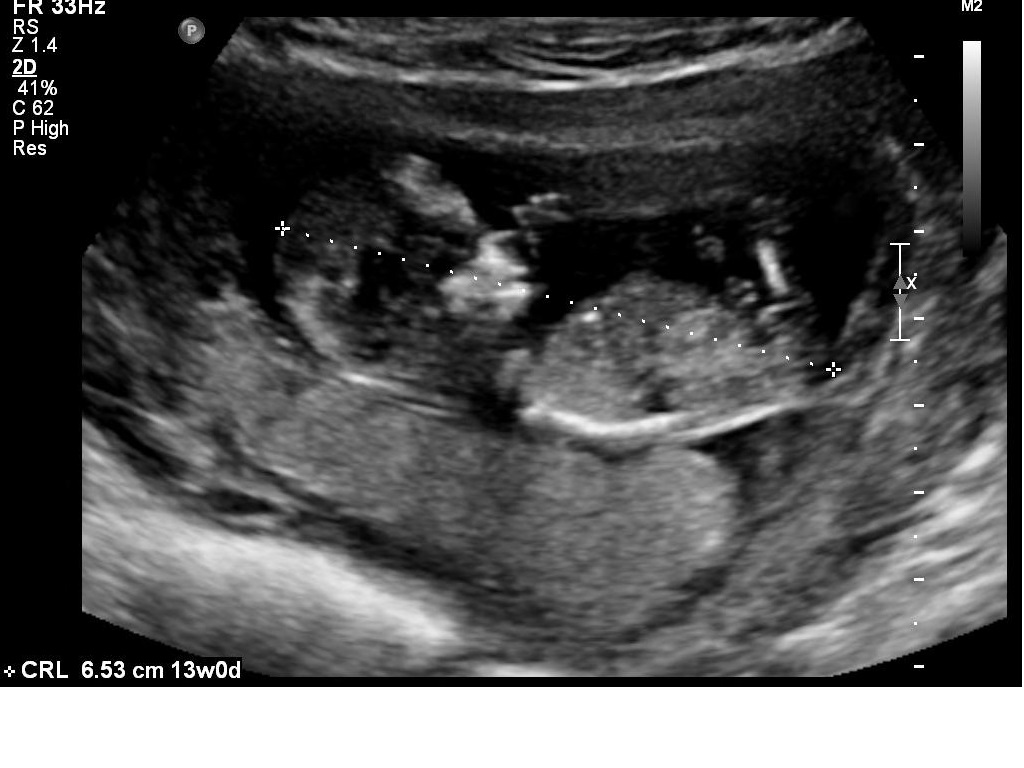

I had my 12w1d ultrasound today, but baby measured ahead at 13 weeks. Bub was very uncooperative and made it hard for the technician to get the NT measurements, which was good in a way because I got to see lots of bub! We got heaps of pictures and I will upload a few here.

I *think* I can tell the gender by the nub pictures but I'd love lots of guesses!!

What do you all think?